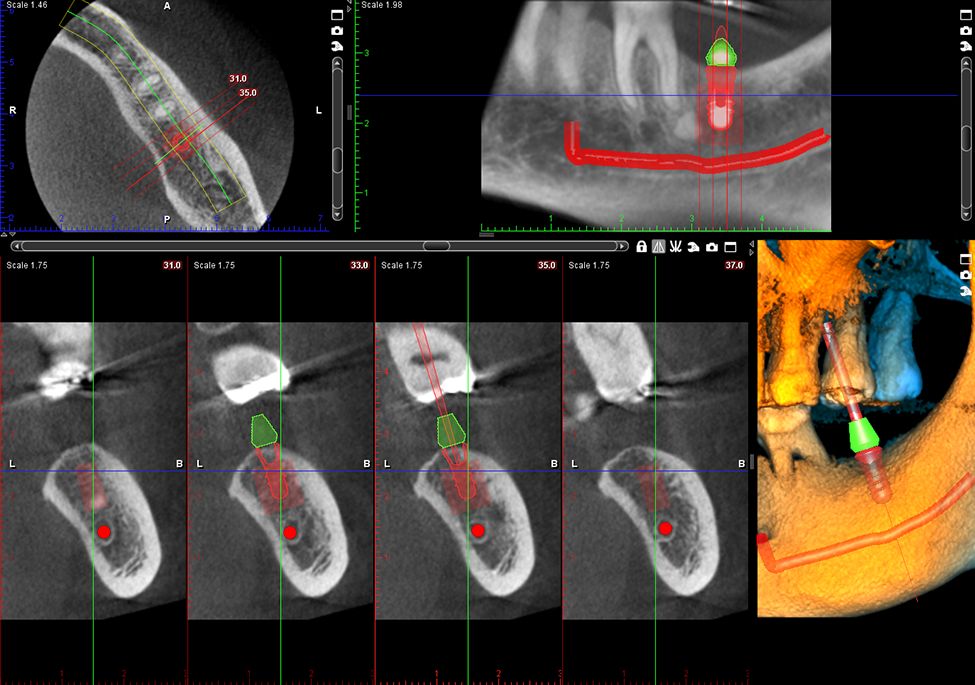

Obrazy Kliniczne Planmeca ProMax 3D s

Szczegółowe obrazowanie 3D

Specjalny tryb obrazowania endodontycznego pozwala na tworzenie szczegółowych, trójwymiarowych zdjęć. Woksele o rozdzielczości 75 μm zapewniają wyjątkową jakość obrazu, uwzględniając nawet najdrobniejsze detale.

• Obrazuje małe obszary z dużą szczegółowością, idealny do implantów i leczenia kanałowego.

Oprogramowanie Planmeca Romexis® oferuje kompleksowe narzędzia do obrazowania przeznaczone dla wszystkich klinik – niezależnie od ich wielkości. Jest to jedyne oprogramowanie stomatologiczne na rynku, które łączy w sobie wszystkie funkcje obrazowania z kompletnym systemem CAD/CAM.